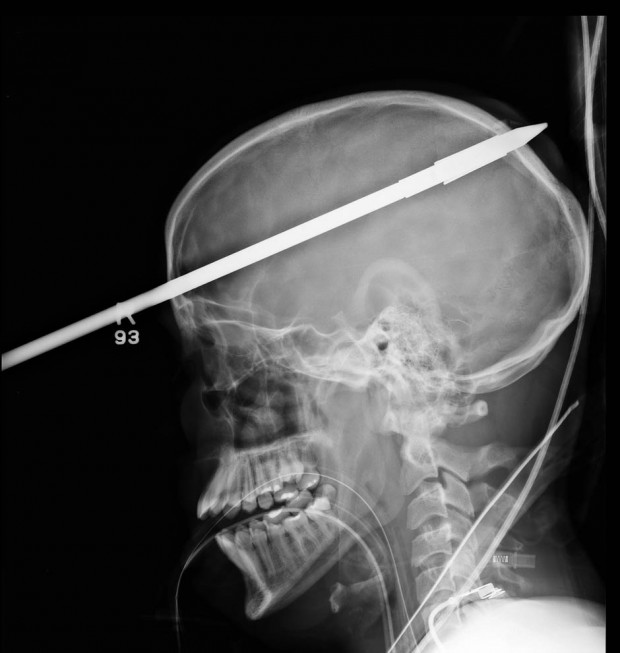

Доктора в Майами были поражены, когда им в больницу доставили 16-летнего подростка с копьем в голове. Несчастный случай произошел на рыбалке, где 16-летний Яссер Лопес ловил рыбу с друзьями с помощью автоматических гарпунов.